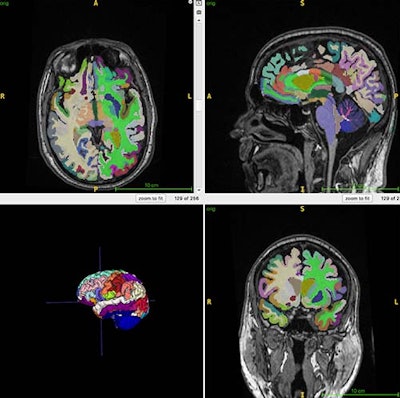

This color-coded brain figure shows an example of segmented regional volumes obtained from the 3D T1 volumetric MRI scans used for the artificial intelligence (AI) computations of brain age used in this study.RSNA

Structural MRI scans can estimate an individual's brain age, while body MRI can track muscle mass -- which can serve as a "surrogate marker for various interventions to reduce frailty and improve brain health," Raji and colleagues explained. Additionally, brain age predicted by structural brain images can lend insight to Alzheimer's disease risk factors, which may include muscle loss.